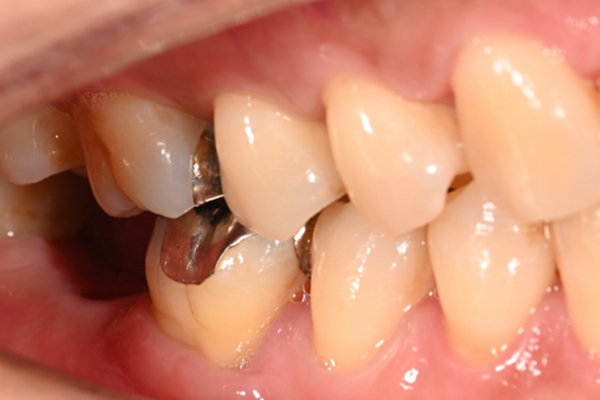

| 主訴 | 歯が痛い |

|---|---|

| 治療内容 | 右上奥歯に対するインプラント治療 (今後右下に対してもインプラント治療を予定) |

| 治療期間 | 6ヶ月 |

| 治療費 | 44万5千円 |

| 治療 リスク | インプラントを埋入したあと3ヶ月程度待ち時間が必要。 その期間は仮歯を使用していただきます。 |